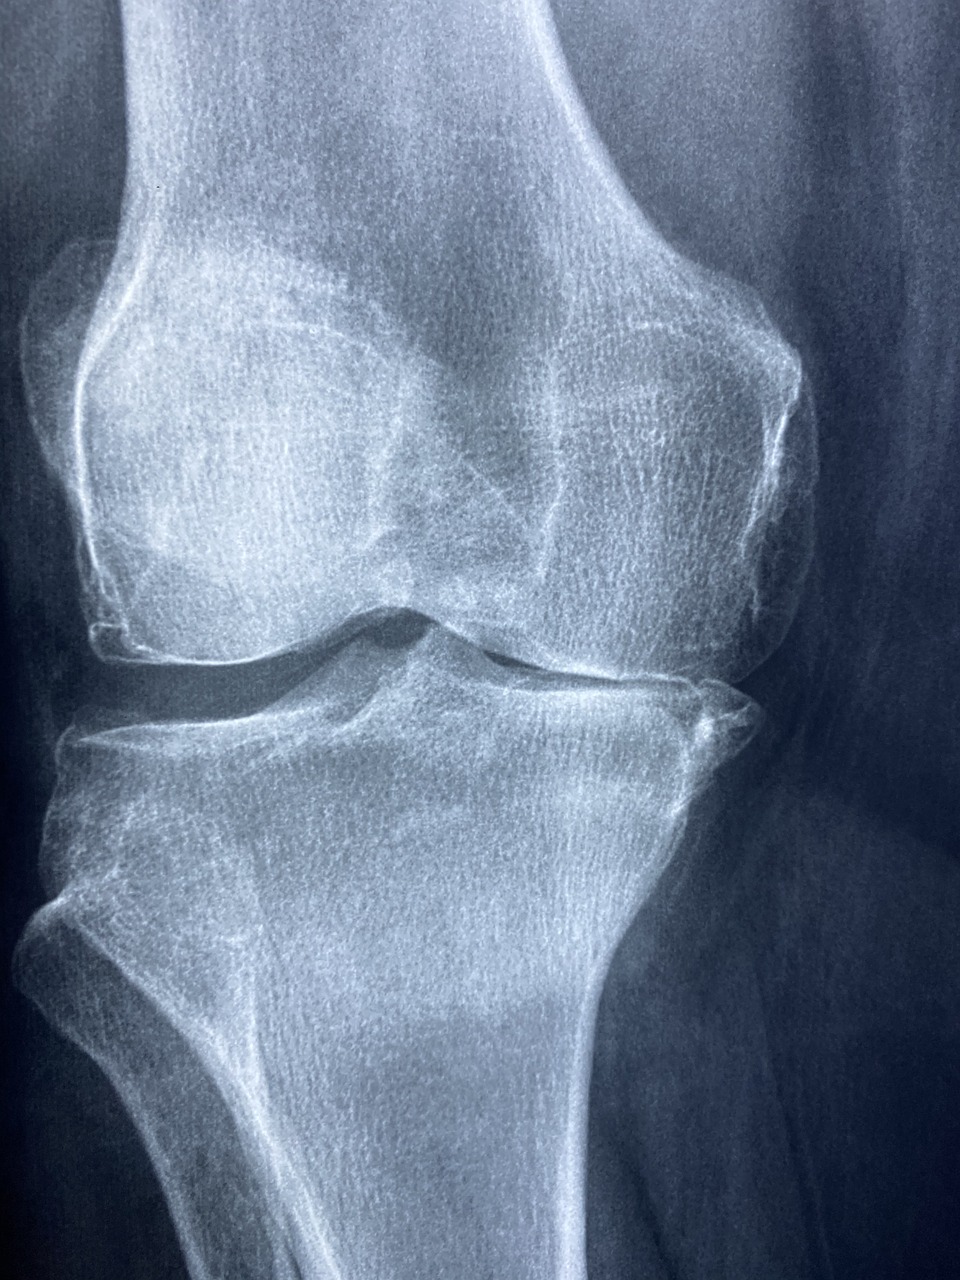

4. 진단 방법

- 가성통풍: 관절액 검사로 결정의 유무를 확인.

- 일반 통증: X-ray, MRI 등으로 구조적 이상 검사.